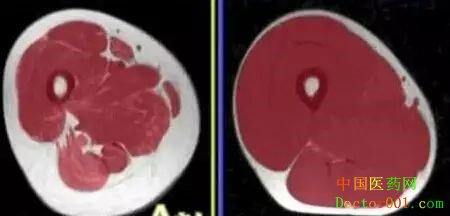

女性在中国社会中扮演着重要的角色和地位,从1968年毛主席提出“妇女能顶半边天”起,至今已经四十多年了,中国女性既打拼事业,也兼顾家庭,确确实实实现并承担了”顶起半边天”的社会责任,中国女性名列前茅的全球就业比例背后,是中国的女性承担着巨大的责任和压力的写实。2011年中华医学会第三次全国绝经学术大会上就曾提出过大的社会和生活压力易导致女性绝经年龄的提前,关注女性绝经期身心健康日渐重要。 围绝经期是指妇女绝经前后的一段时期(从45岁左右开始至停经后12个月内的时期),包括从接近绝经出现与绝经有关的内分泌、生物学和临床特征起至最后1次月经后1年。 围绝经期女性卵巢功能衰退、雌激素水平降低,这将导致女性生理心理的改变。生理的改变则主要为人体组成的变化,如: * 体脂肪增加,腹部脂肪堆积。

* 肌肉含量下降

* 骨矿物质含量

* 身体水分丢失

通过定期进行人体体成分分析测试,如使用InBody体成分分析仪进行测试,可以帮助临围绝经期或围绝经期女性很好的掌握自己身体各项体成分的状态,从而采取对应的措施减少围绝经期对女性产生的生理以及心理影响,帮助女性更好地度过围绝经期。

InBody体成分分析报告纸 滨州医学院护理学院从身体成分的角度研究了不同生活方式对围绝经期女性的影响[1]。 研究以问卷的形式分析运动习惯、饮食饮水水平和夫妻关系对围绝经期女性人体成分的影响,结果发现: 1中强度规律运动有利于围绝经期女性人体成分的改善研究对运动习惯进行分类: 1)规律性-每周运动5次以上,中等强度,每次30分钟以上; 2)一般型-每周活动2-4次,低强度,每次30分钟以下; 3)非活动型-偶尔活动或者不活动; 运动习惯规律性女性的体成分在脂肪、肌肉、水分、骨量、腰臀比方面均表现优于其他型女性,而一般型与非活动型女性几乎无差异。这是因为一定强度及一定持续时间的运动可以燃烧脂肪、增加骨骼肌对葡萄糖的社区利用,改善脂质代谢,增强抗氧化酶活性,减少脂类过氧化代谢产物,促进新陈代谢、增强肌肉力量和耐力、促进钙的吸收、降低骨量丢失速率。 2饮食饮水可以优化围绝经期女性人体成分研究根据围经期营养知识了解程度、对膳食搭配的执行情况、饮水情况进行分类: 1)重视型-规律合理的膳食搭配,每日饮用牛奶,食用豆制品,定时饮水达每日1500ml; 2)非重视型-思想上不重视或缺乏营养知识; 3)一般型-介于两者之间; 饮食饮水习惯可显著改善围绝经期女性脂肪、肌肉、骨量和腹型肥胖情况。这与合理膳食习惯有利于肥胖改善,相关营养素的补充有关。 3和谐的夫妻关系亦可以调节人体组的改善和谐的夫妻关系包括和谐的性生活和良好的夫妻感情,这可以维持体内激素平衡,进而维持和促进骨基质代谢,有利于预防冠状动脉硬化。